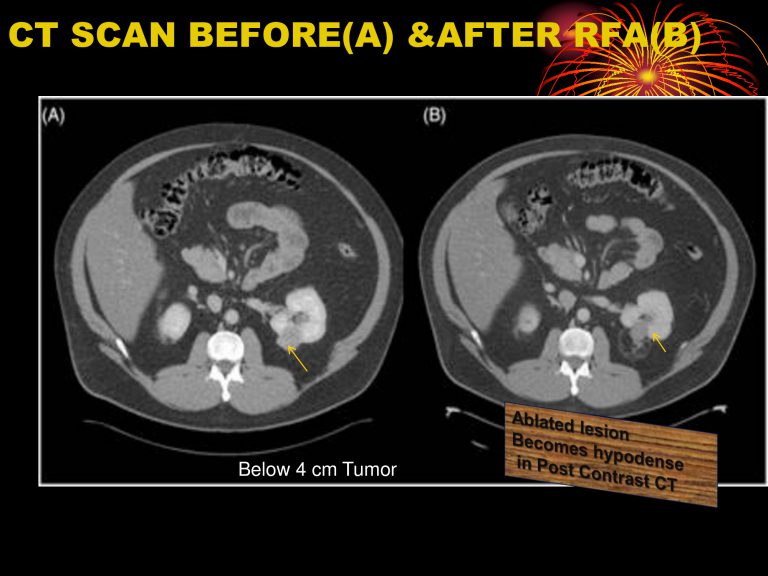

১) যাদের কিডনী ক্যান্সার টিউমার ৪-৮ সে.মিঃ তাদরে RFA, MWA দিয়ে চিকিৎসা মাধ্যমে ৯০%-৯৮% রোগীর ক্যান্সার সম্পূর্ন নিমূল করা সম্ভব। এছাড়াও যদি পুনরায় দেখা যায়,তবে আবার RFA, MWA চিকিৎসা করে ক্যান্সার টিউমার নিমূল করা যায়। ইদানিং বিভিন্ন ক্যান্সার সেন্টার ৪ সেমি. এর নীচের টিউমার গুলোর প্রাথমিক চিকিৎসা হিসেবে RFA বেছে নিচ্ছে। যাদের কিডনি ফেইলোরের সম্ভবনা আছে বা কিডনি নষ্ট হয়ে আছে তাদের জন্য RFA ভালো চিকিৎসা। যার ফলে কিডনি কে আরও ভালো রাখা সম্ভব এবং সুস্থ ও সাভাবিক জীবন যাপন সম্ভব।